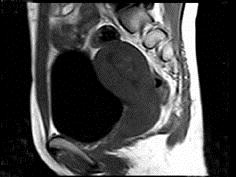

问题 35岁女性患者,曾行剖宫产手术,有痛经史5年,近来加重,行MRI检查,如图所示,请选择正确的答案 ( )

选项 A、卵巢表皮样囊肿 B、卵巢粘液性囊肿 C、子宫颈癌 D、卵巢囊肿 E、子宫内膜异位症

答案 E